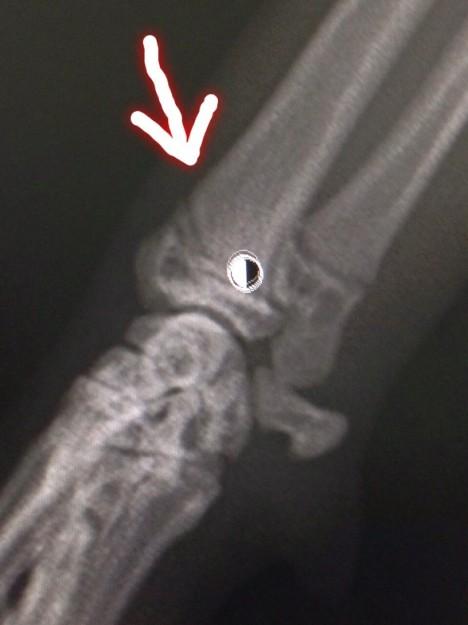

二枚のレントゲンの写真を撮りました。

結果 どーも ひびが入ってた ようです。

この程度だったら 何をすることもなく ほっとくらしいw

きっとケージによじ登り。。。腕が入ったまま ねじれたのではないか?

って 見解でしたw